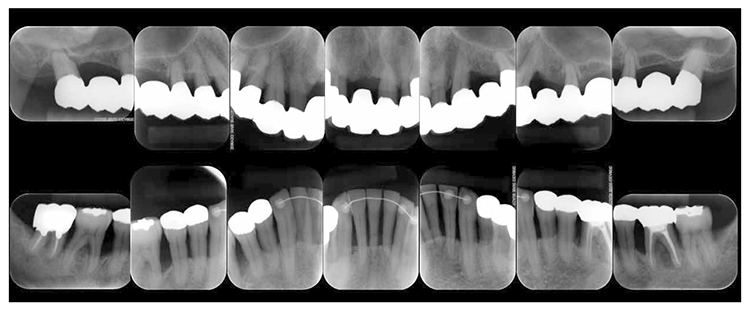

8)SPT (December 2013 onward)

After transitioning to SPT, the patient brushed 4 times daily after every meal and before bedtime and has continued to use an interdental brush. PCR levels have been consistently in the 20% range. SPT , which primarily consists of instructions on brushing and dental surface cleaning, has been implemented every other month to present, and efforts are made to maintain and manage oral hygiene in the long term to ensure that plaque control is not insufficient. While minor discoloring is observed on the prosthetics, the color of the gingiva is salmon pink and a macroscopically healthy appearance has been sustained (Fig.7a) . The average PD on the entire jaw is 2.1mm,maximum PD is 4.0mm,the ratio of PD of 3mm or less is 99.3%. No BOP has been found and the condition of the periodontal tissue has been stable (Fig.7b). In the X-ray, continuity of the alveolar hard line has been replicated and the sequence of the bone trabeculae has been normal (Fig.7c).

Fig 7c

(Fig.7c) 15 years after first visit: dental X-ray 14 (December 2022)